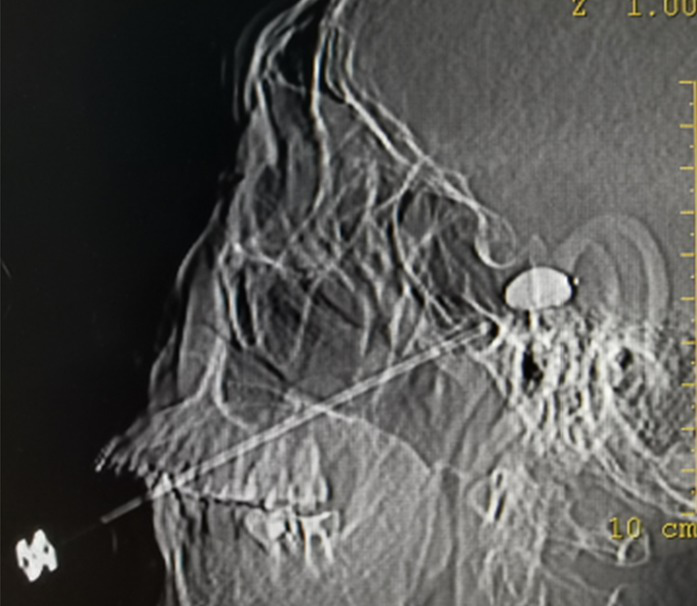

This study performed PRT and PBC under computed tomography (CT) guidance and local anesthesia. Patients were not required to fast before surgery; however, intravenous fluids were administered to ensure intravenous drugs were administered when necessary. CT helps in improving puncture accuracy. Therefore, we scanned the position of the puncture needle using CT and reconstructed the anatomical image of the skull base of the patient by three-dimensional CT imaging technology. The relationship between the puncture tip and the anatomy of the skull base was visible.

Furthermore, CT-guided imaging has been widely used in PRT; however, it has not been widely used in PBC. Three-dimensional (3-D) imaging reconstruction produces more efficient and safer results than two-dimensional imaging (14). Preoperative three-dimensional imaging reconstruction of the skull base helps detect anatomic variations and avoid inadvertent injury to the peripheral neurovascular structures (15). Furthermore, the CT-guided approach reduces the number of operational adjustments and minimizes potential damage to the oculomotor and abducens nerves. Diplopia or keratitis is effectively eliminated, with historical incidences ranging from 1–4% and 5–12%, respectively (16, 17). The location of the foramen ovale and the depth of penetration of the cannula is visible, which gives the surgeon confidence and greatly improves patient safety. In addition, 3D reconstruction is more effective and accurate than other techniques in patients with perivale bone herniation and prevents successful intubation using conventional techniques. Our operations were all performed using CT, which differs from traditional surgery.